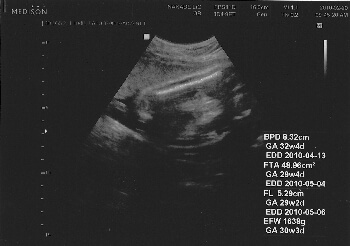

妊娠8ヶ月(妊娠29週目):妊婦検診

妊娠後期の妊婦検診。赤ちゃんの発育以上に自分の体重が増加してます。 -